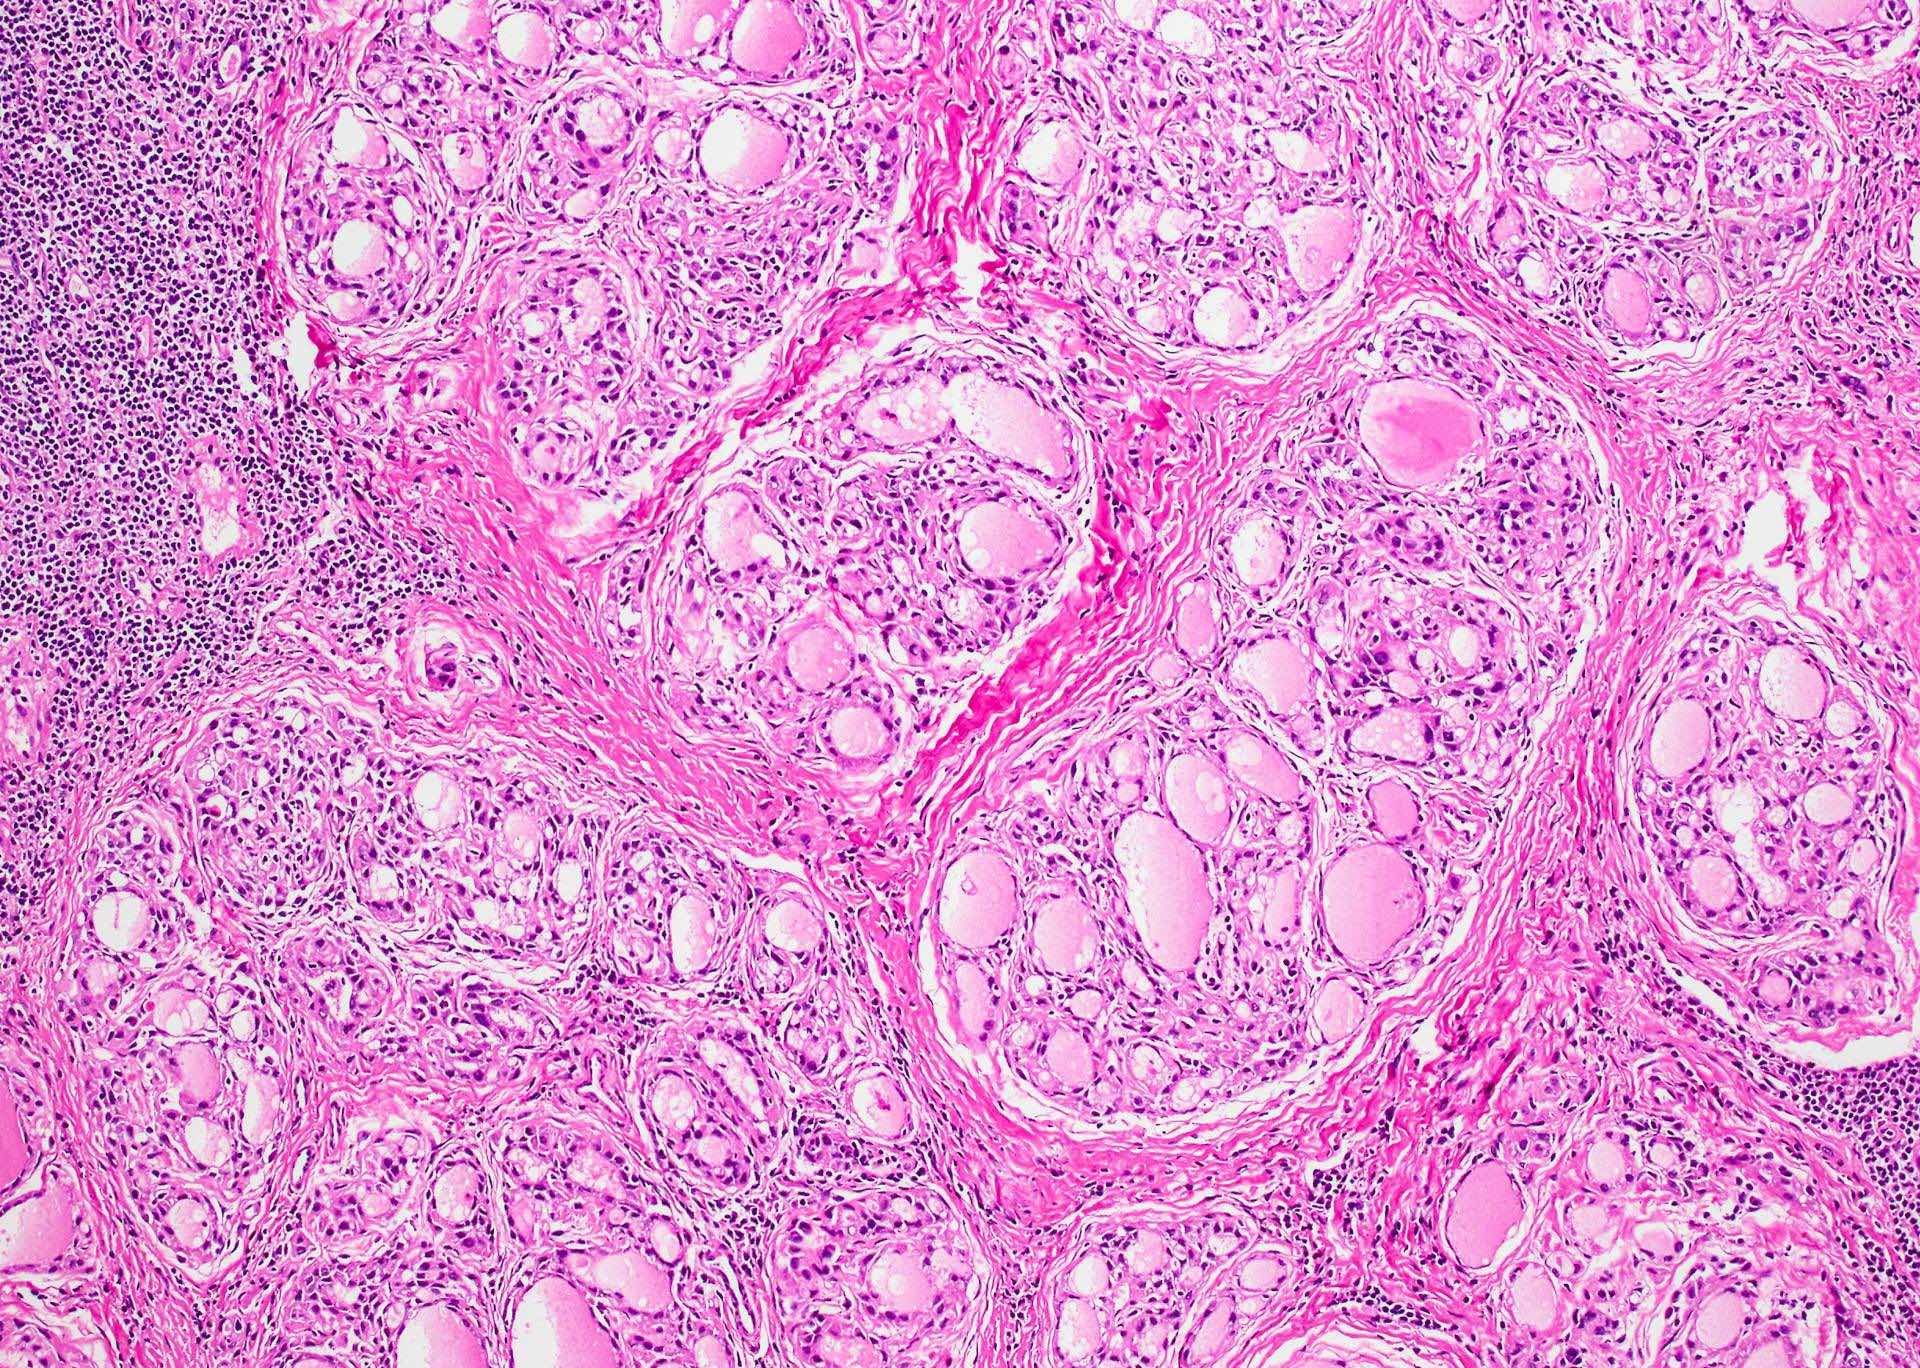

(PDF) Hashimoto’s thyroiditis with granulomas A unifying immunological

(PDF) Hashimoto’s thyroiditis with granulomas A unifying immunological Bromelain Hashimoto's Thyroiditis Hashimoto thyroiditis is an autoimmune disorder that presents with or without signs or symptoms of hypothyroidism, often with a painless goiter, and is associated with elevated. Hashimoto thyroiditis, also known as chronic autoimmune thyroiditis and chronic lymphocytic thyroiditis, is an autoimmune disease in which thyroid cells are destroyed via. Hashimoto’s thyroiditis is also known as chronic lymphocytic thyroiditis or autoimmune.. Bromelain Hashimoto's Thyroiditis.